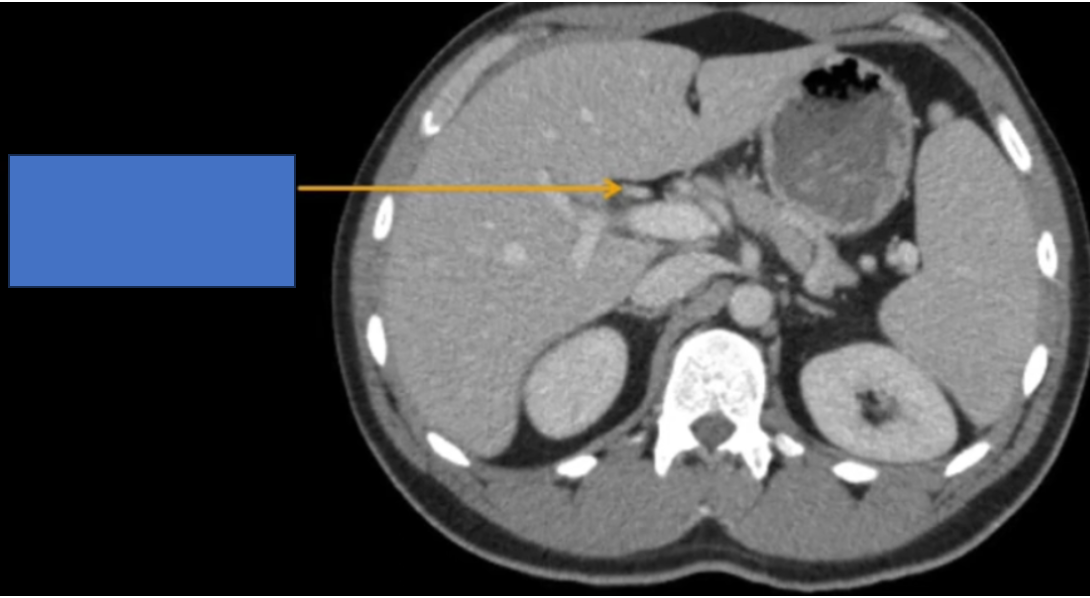

TM gan ở đâu? TM chủ dưới ? ĐM chủ?